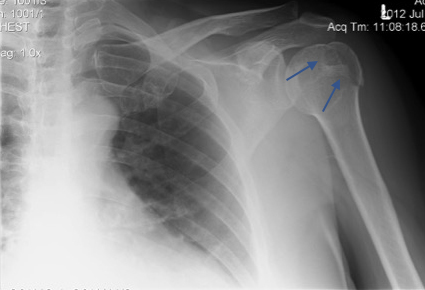

Lesson 4 / An acromioclavicular joint (ACJ) disruption can fool the unwary into thinking they have a dislocation to deal with.

A grade 3 ACJ injury results from separation of the AC joint (and the coracoclavicular ligament as well) producing a step that you might think is a dislocation. However, the step is at the level of the ACJ and the round shape of the shoulder is preserved as shown in the picture below.

This greater tuberosity fracture explains why the patient can’t abduct the arm: supraspinatus, infraspinatus, and teres minor all insert here.

Lesson 8 / Think about the structures that you can’t see on the plain x-ray.